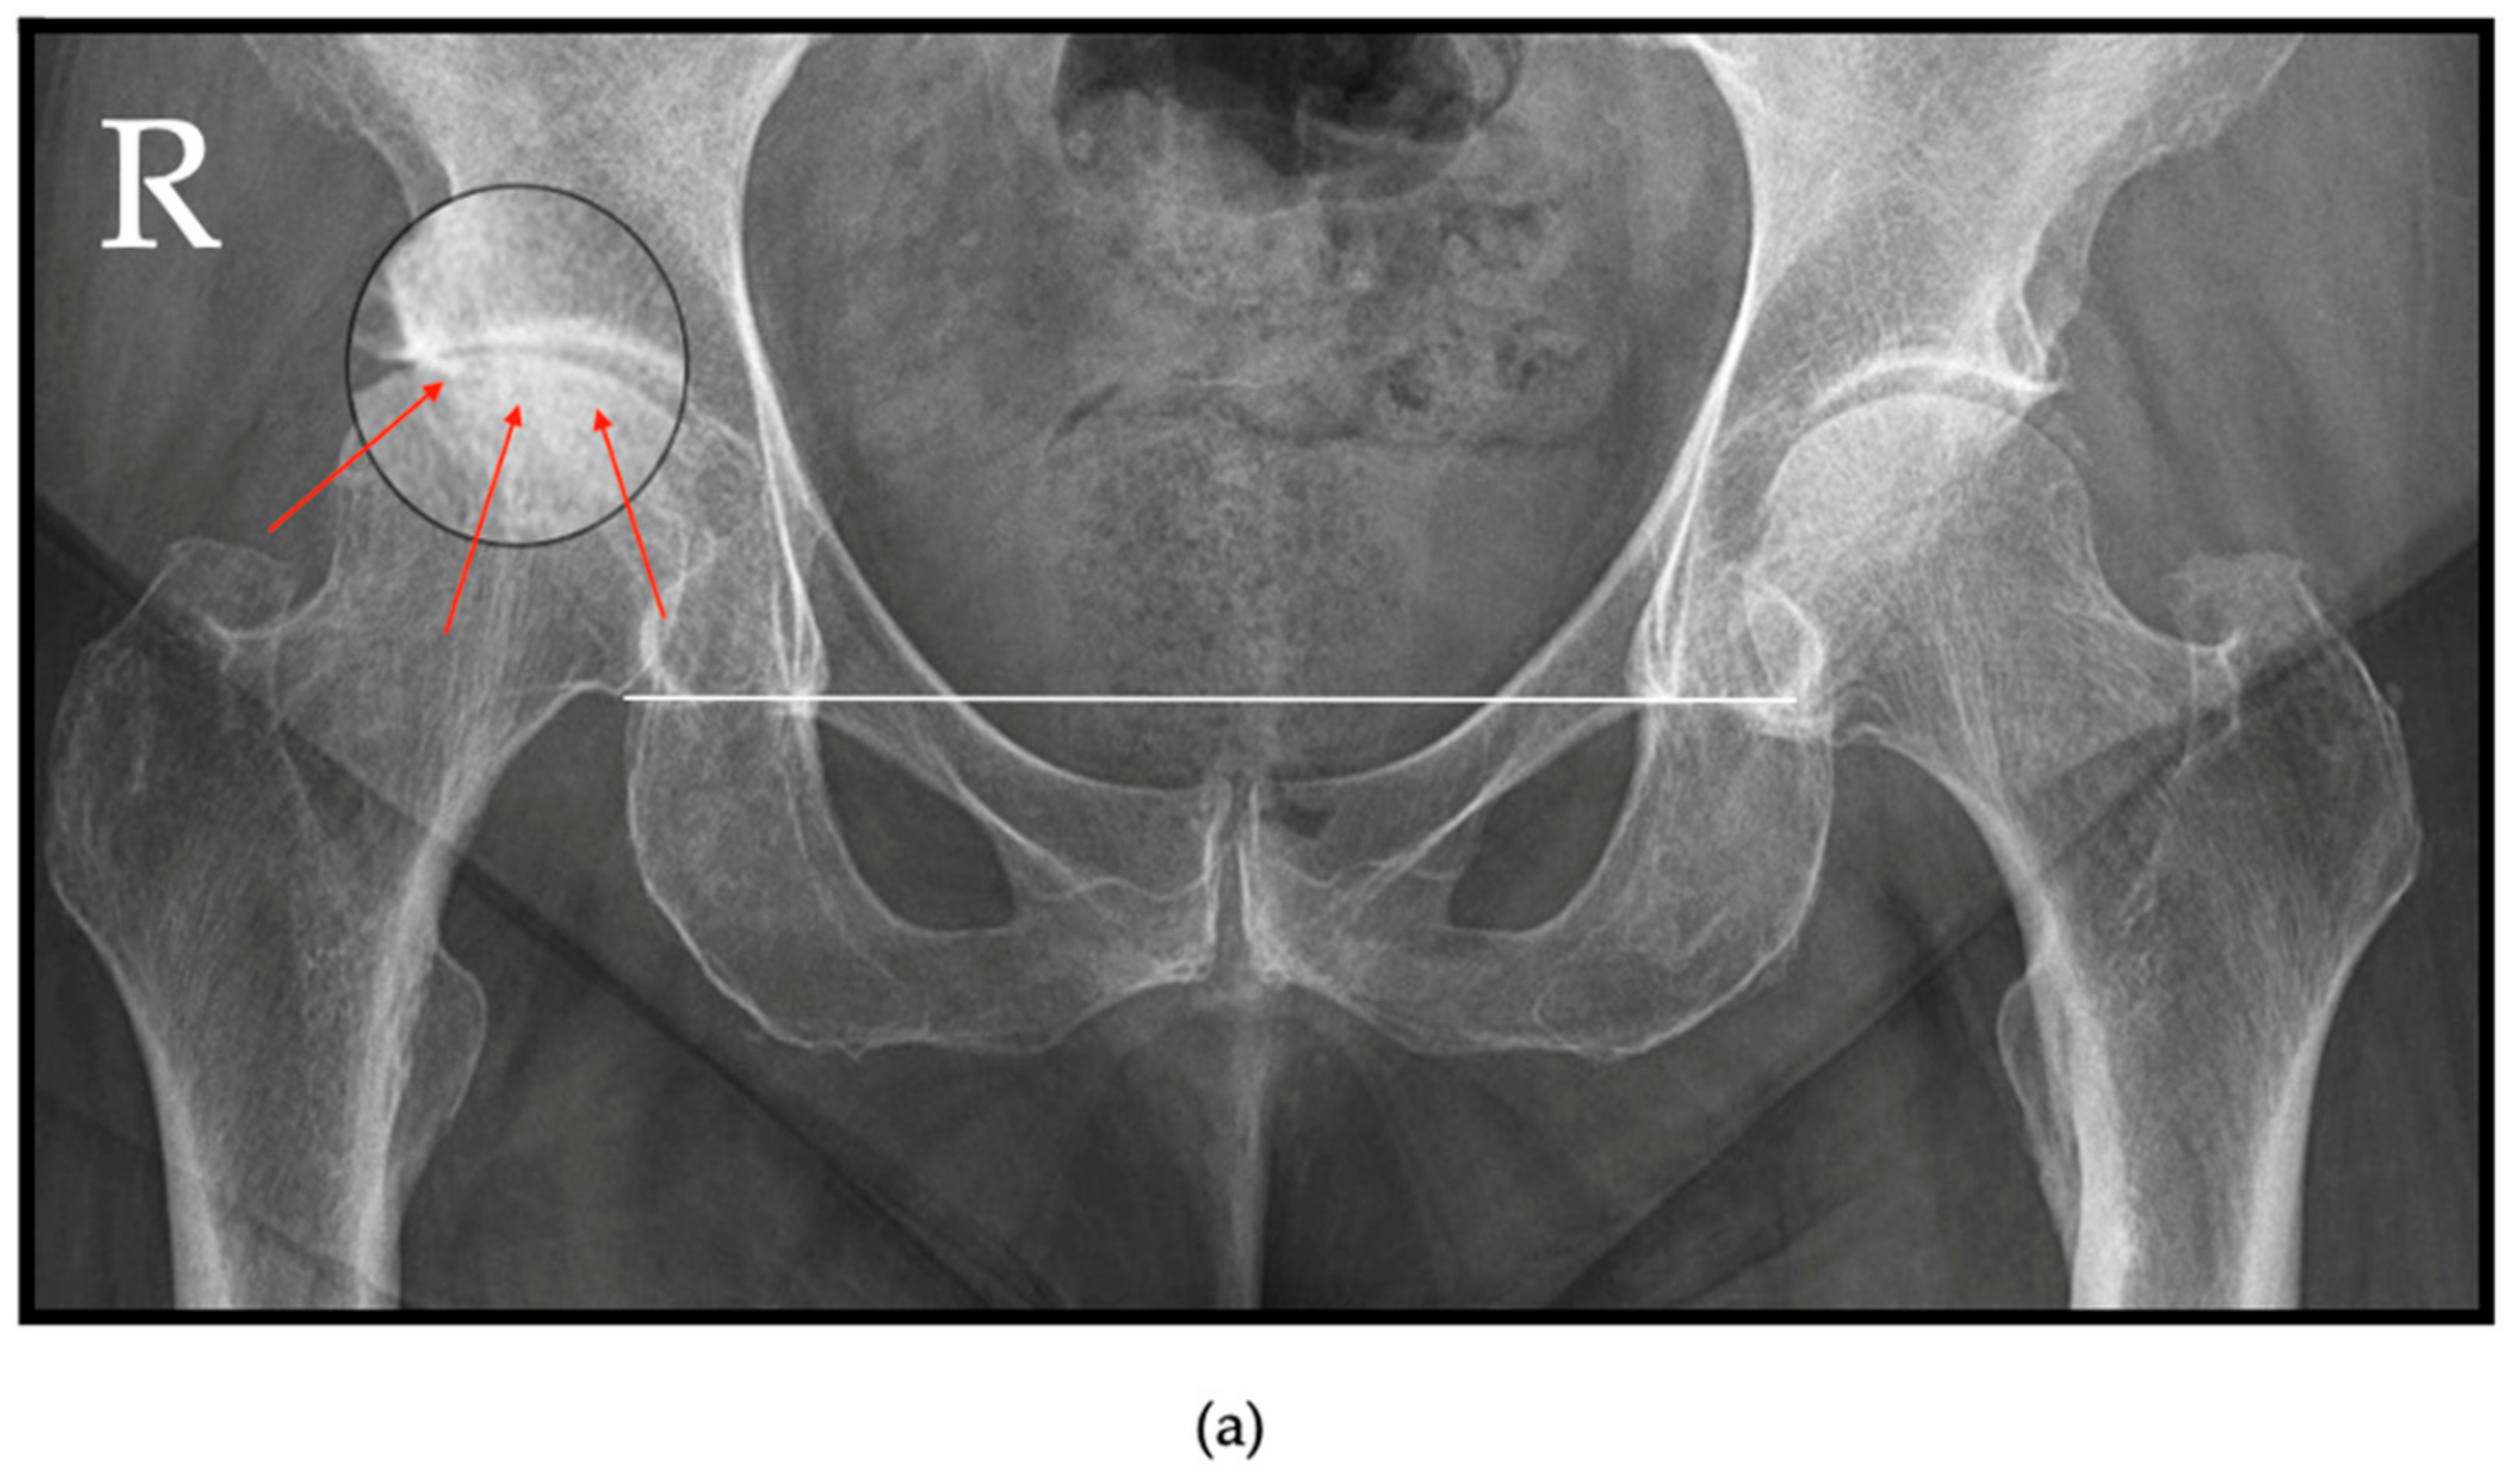

6.1. Radiographs

| Grade II | Complete disappearance of the joint space; deformed femoral head and acetabulum; femoral head ascension ≤ 0.5 cm above radiologic teardrop. | ||

| Grade III | Complete disappearance of the joint space; partial osteolysis of the femoral head; femoral head ascension > 0.5 cm above radiologic teardrop. | ||